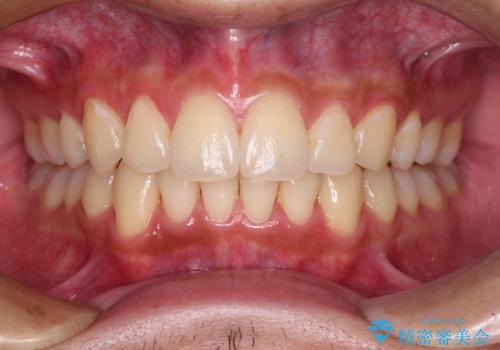

矯正治療後は、再度後戻りすることを極力回避するために、下顎前歯の舌側を細いワイヤーを用いて保定することとしました。

- 9ヶ月

- 5-10回